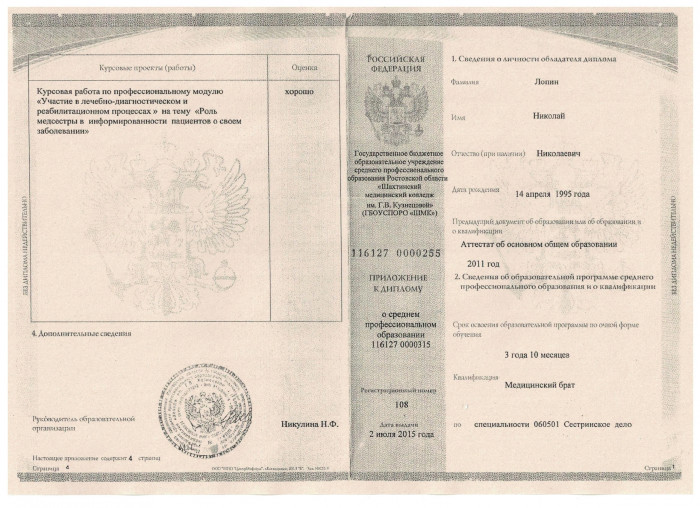

Лицензии и сертификаты

Лечение в нашей клинике анонимно, поэтому никто не узнает, что вы проходите или проходили лечение в нашем наркологическом центре.

Лицензии и сертификаты нашей клиники

Медицинские услуги оказываются ООО "ЮгЭкоСервис+" по лицензии ЛО-61-01-008143 от 28.12.2021 г.